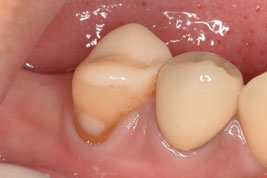

「日本よりも素晴らしい医療を受けることができそうなヨーロッパの国」から来院された方です。在住先の複数の歯科医院で右下5番の根管治療を断られたため、日本での治療を希望され来院されました。

右下6番も根管治療を断られてしまい、痛みが酷かったため抜歯したそうです。抜歯してからも強い違和感と腫れが続いているそうです。前医で撮影したレントゲンデータをもとに、処置を進めることとしました。

先生だったらこの写真で右下5番を抜歯判定しますか?どう考えても、まずは保存を第一選択とするはずです。しかし、先進的な国であればあるほど、皮肉にも抜歯になってしまうのです。

広範囲に軟化象牙質を認めましたが、歯肉縁上に十分な健全歯質を保存できたため、根管治療を施術しました。前医での複数枚のレントゲン写真があったため、そちらを参考に処置を進めました。